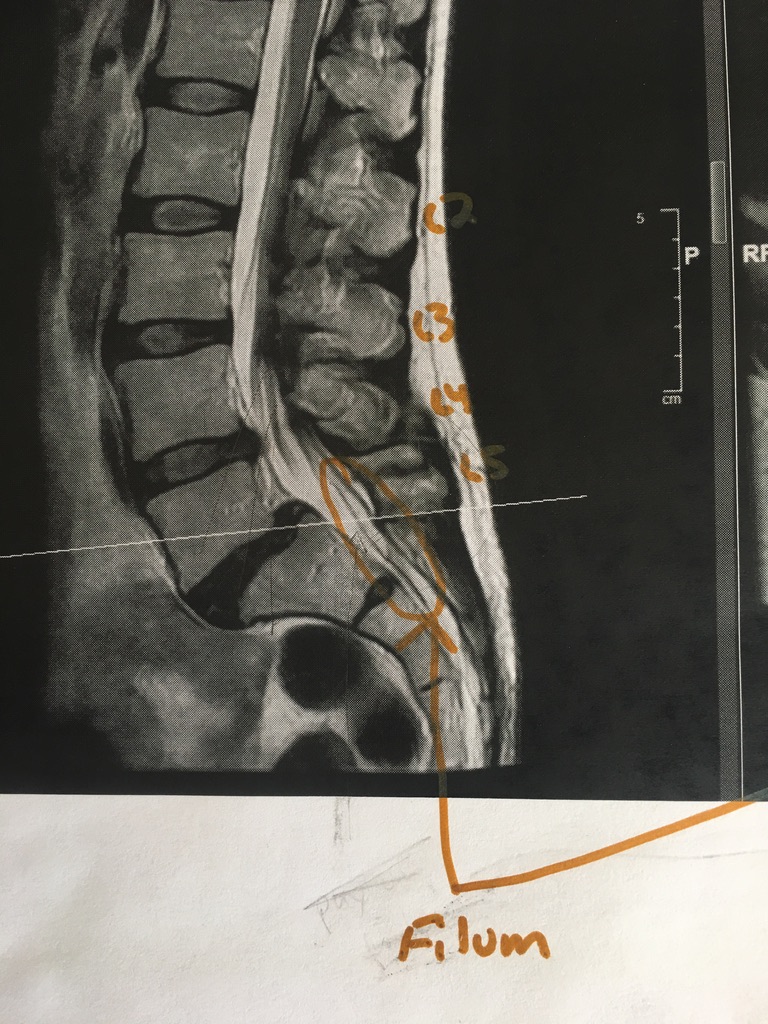

Here the tethered filum is circled.

Several spinal specialists saw this same imaging and did not note this.

Close-up of the filum. This is what Dr. Klinge cut out and removed. The texture was tough, like grizzled meat, apparently – which is typical of tethered filums.